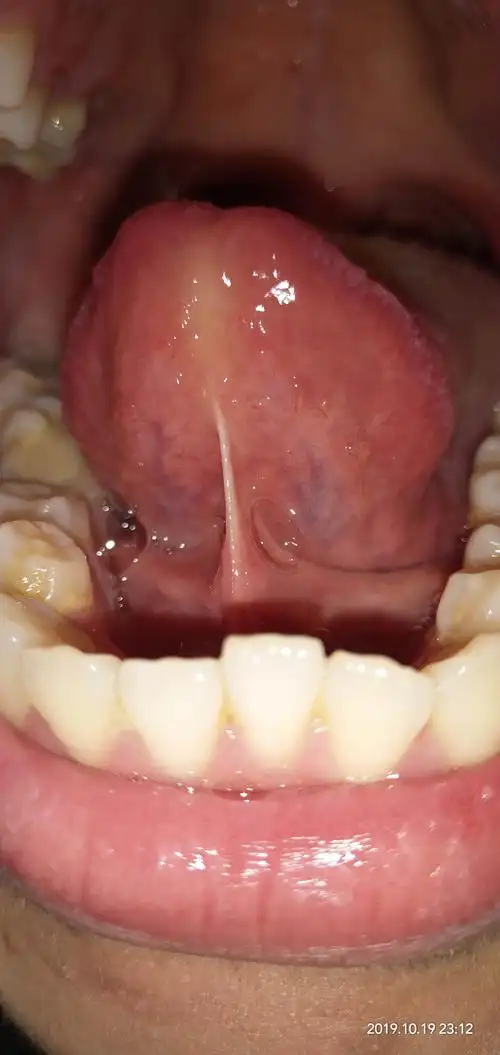

舌下络脉短细,周围小络脉不明显,气血不足